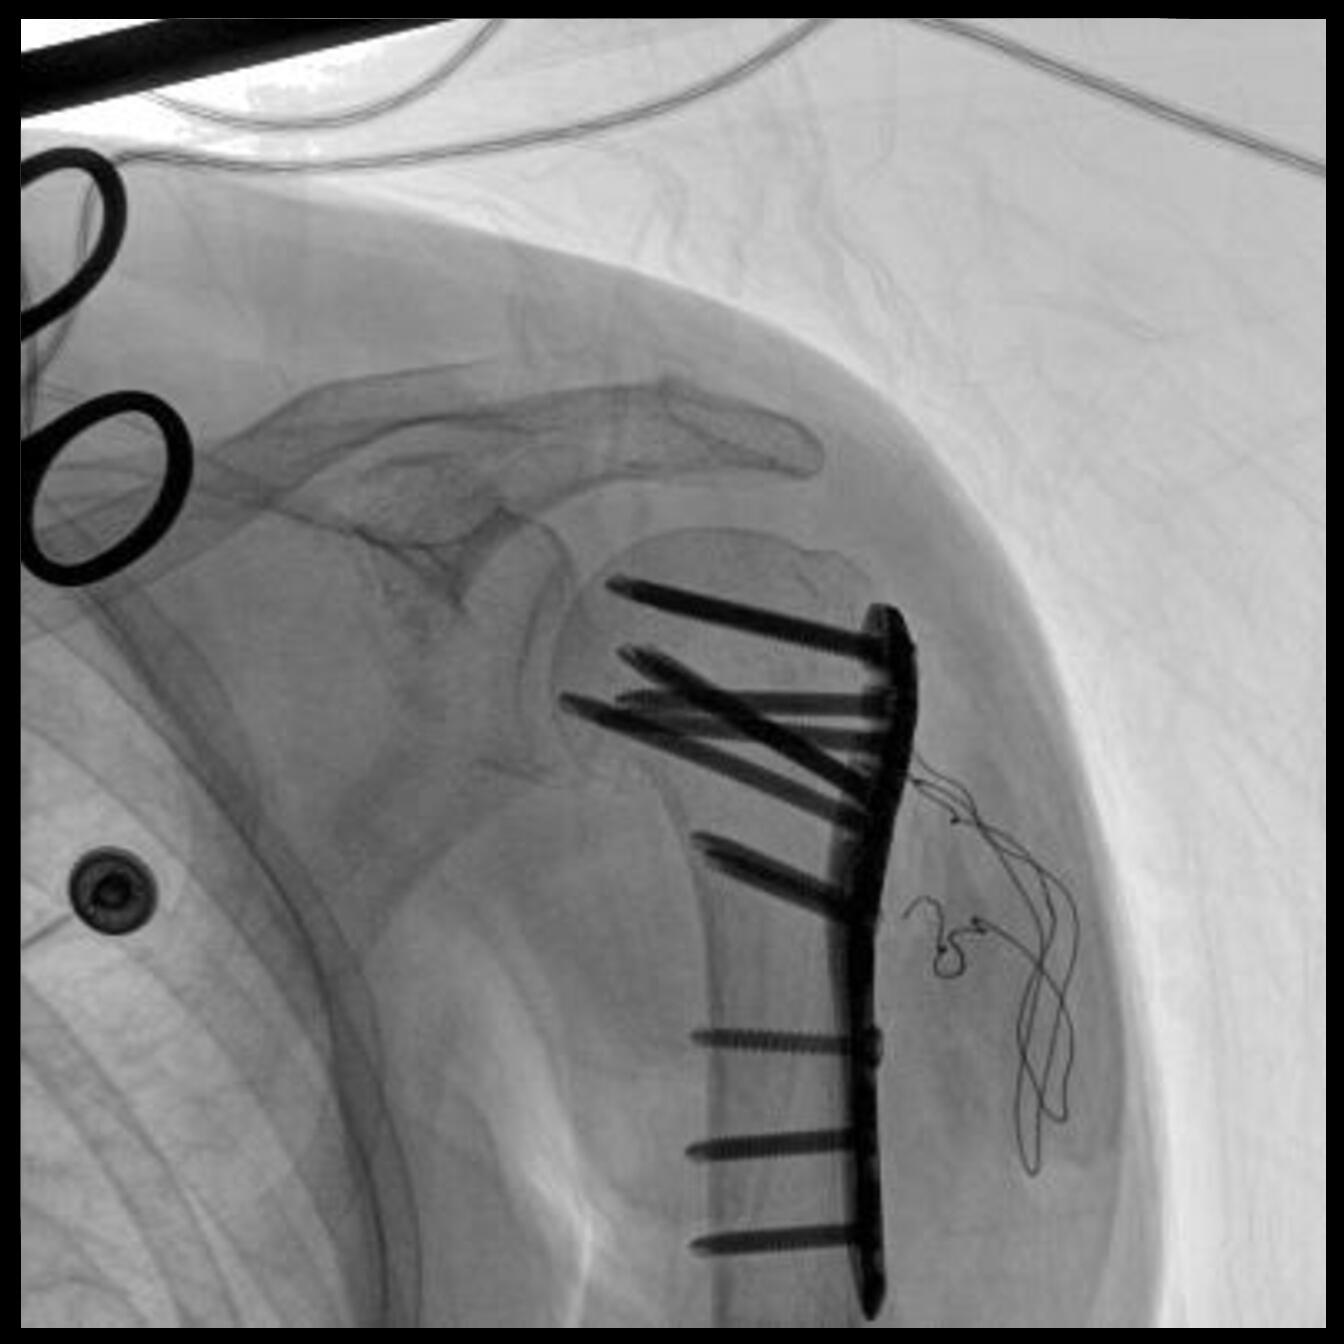

PLX118F-Plus配備了兩種平板尺寸,大尺寸動(dòng)態(tài)平板探測器成像面積較傳統平板探測器提升了25%以上,在視野需求大的手術(shù)中,便于醫生更好定位病灶點(diǎn),規劃手術(shù)方案,減少因視野范圍不足而多次透視、點(diǎn)片造成的不便。

Clinical picture

臨床圖片